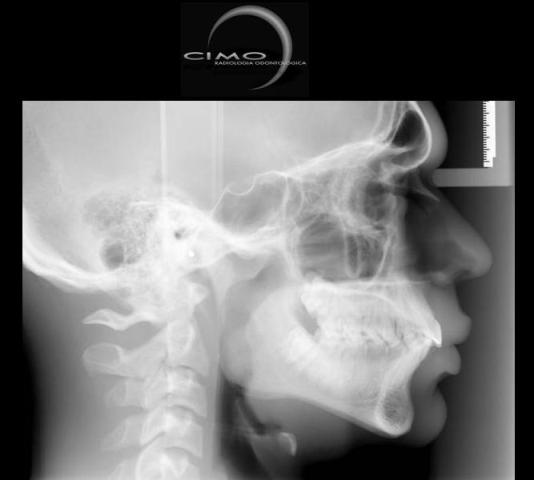

TELERRADIOGRAFIAS

Lateral e Frontal

Radiografias do crânio, realizadas a uma distância pré-estabelecida, com o objetivo de diminuir distorções, com o auxílio de um artefato posicionador – cefalostato. Permite mostrar os ossos da face e crânio para avaliação do crescimento, desenvolvimento, relação esqueletal, simetria, estudo de adenóides, processos patológicos e traumáticos. São exames utilizados na prática cirúrgica e ortodôntica, como base para análises cefalométricas, tanto manual como computadorizada.

* Telerradiografia Lateral